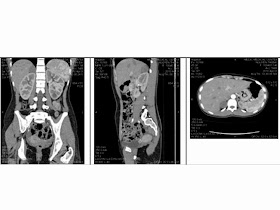

MSCT with CE: this mass was in retroperitoneum compressing duodenum

D2,

contrast injection was slowly enhancement , but it had air in the  mass ( see 4 CT  with CE pictures CT1, is angiogram of right

axillary artery, CT2. this mass with air inside, CT3, relation with right

kidney and aorta, CT4 vascular SMA and mass).